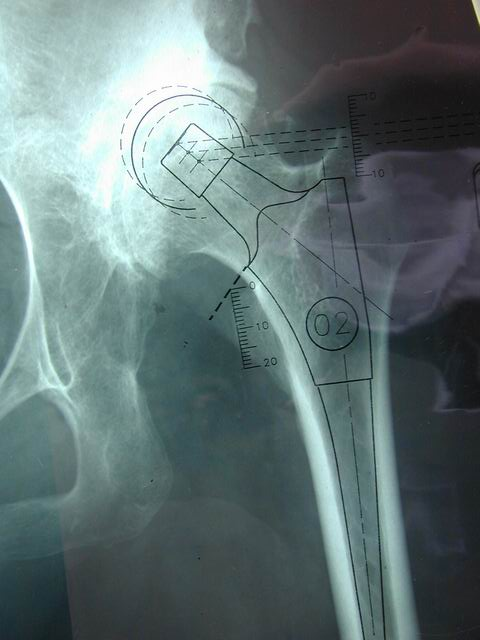

如何恢复offset及双下肢等长术前评估及模板测量术中评估

确定正常侧髋关节的旋转中心镜像至患侧:

确定股骨颈截骨线对侧髋关节正常,可以对侧为参照

-选择合适的颈长(一般将设计的颈长定为中颈,以保留适当的调整余地)

-将假体股骨头的旋转中心与髋臼假体的旋转中心相吻合

-定出截骨高度(可以小粗隆为参照)

-镜像确定在患侧的截骨高度

确定股骨假体的大小1、在截骨位置正确选择股骨假体的尺寸2、需考虑股骨在侧位片上的匹配程度